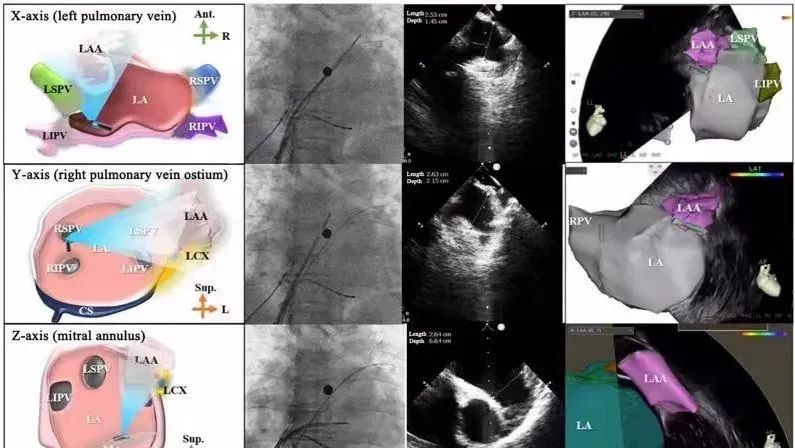

一種與心導(dǎo)管檢查相結(jié)合的超聲心動圖診斷新興技術(shù),通過將超聲探頭置于心腔內(nèi)部,發(fā)射并接收超聲信號,來精確獲取心臟解剖結(jié)構(gòu)、心臟血流動力學(xué)等信息的實時成像。與其他影像技術(shù)相比,ICE技術(shù)具有操作簡單、無輻射、安全性高、手術(shù)效率高、實用等優(yōu)勢,ICE在很大程度上有望取代經(jīng)食道超聲心動圖(TEE),成為電生理和結(jié)構(gòu)性心臟病領(lǐng)域的理想成像方式。

心腔內(nèi)超聲(ICE)技術(shù)壁壘極高,國內(nèi)主要廠商核心部件仍舊為進(jìn)口,集成了超聲和圖像處理最前端技術(shù),包括超聲探頭、線纜、軟件成像算法等,是當(dāng)前內(nèi)窺超聲方向最具挑戰(zhàn)的領(lǐng)域。ICE的應(yīng)用經(jīng)歷了2D平面成像、3D三維立體成像、以及4D的實時三維立體成像階段。